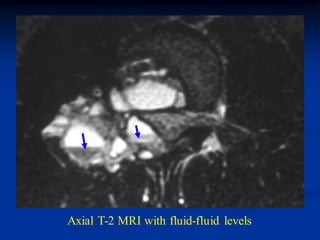

Case #202

17 year male with ABC mid lumbar vertebra

Ct scan

Coronal T-1 MRI

Axial T-2 MRI with fluid-fluid levels